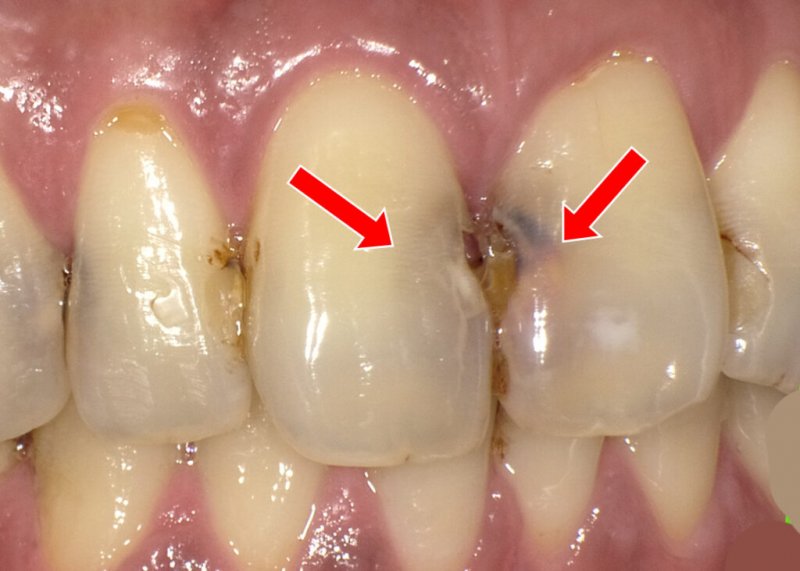

**歯髄炎(しずいえん)**とは、歯の内部にある「歯髄(神経)」が虫歯や外傷、細菌感染によって炎症を起こす病気です。

進行すると激しい痛みを伴い、放置すれば神経を抜く「抜髄」や、最悪の場合は抜歯が必要になることもあります。

虫歯の進行:C2でしみ始め、C3に達すると激痛。

細菌感染(バイオフィルム):ミュータンス菌などが原因。